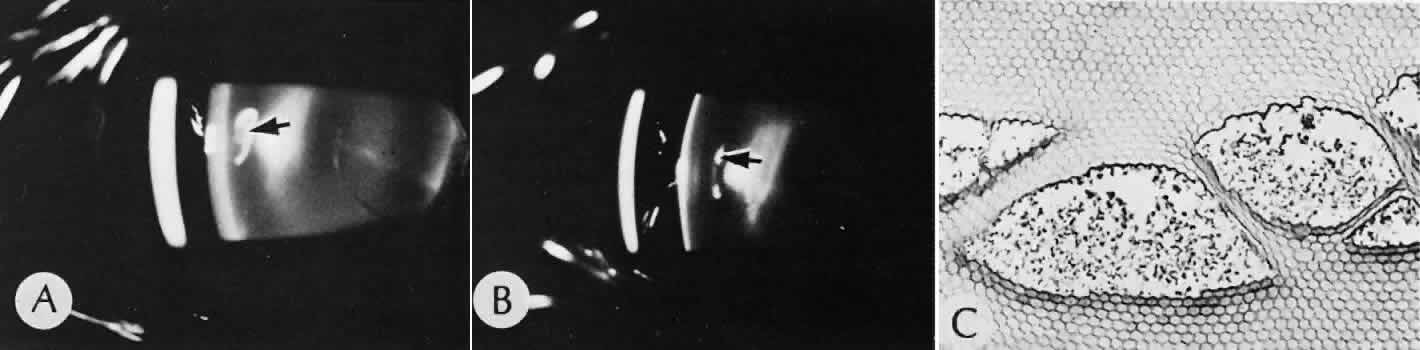

Elschnig's pearls (Fig. 41) result from aberrant attempts by lens cells attached to the lens capsule to form new lens “fibers.” Histologically, large, clear lens cells (“bladder cells”) are present behind the iris, in the pupillary space, or in both areas.

Fig. 41. Two cases of Soemmerring's ring cataract (retained lens cortex and capsule). A. Extensive opaque, well-delineated material is present in a ring-shaped configuration following a partially successful cataract extraction. The opacity is delimited by the remaining lens capsule and is located primarily in the region of the lens equator. B. The eye was examined at autopsy. The reaction is limited to the posterior chamber and within the lens capsule. Surrounding lens zonules and ciliary epithelium are not affected. C. Lens cortical material is retained in the equatorial area of the lens. This area is the least surgically accessible during cataract extraction and contains the tissue most likely to be left behind. This area also contains the cells with the greatest ability to react to trauma by undergoing fibrous metaplasia. The process is identical to anterior subcapsular cataract formation stimulated by anterior chamber inflammation. (Hematoxylin-eosin stain; × 6.) D. Residual lens cortical material ® can be clearly identified entrapped by residual lens capsule. The reaction in the lens may change the adhesive nature of the remaining anterior lens capsule. Posterior anterior synechia may form in these areas. (Hematoxylin-eosin stain; × 16.) E. In another case of retained lens material, the tissue change is less extensive and more translucent, resulting in pearl-like structures (Elschnig's pearls). The process producing this change is the same as the one in Soemmerring's ring formation, but the reaction is less extensive. Pearls are formed by aberrant attempts by lens cells to form new lens fibers. (Hematoxylin-eosin stain; × 69.)

Soemmerring's ring cataract results from the loss of anterior and posterior cortex and nucleus but with retention of equatorial cortex. Apposition of the central portions of the anterior and posterior lens capsule causes a doughnut configuration. Frequently, the doughnut is not complete, so that C- or J-shaped configurations result. Histologically, two balls of trapped and proliferated lens cells are encapsulated behind the iris leaf and connected by adherent anterior and posterior lens capsule in the form of a dumbbell.118

Delayed complications of intraocular lenses themselves are infrequent. The incidence of posterior capsular opacification ranges between 11% and 46% in this period, apparently lower in the presence of an intraocular lens than with extracapsular cataract surgery alone.119,120 Histologically, residual lens epithelial cells are transformed into cells with myofibrillar contractile properties, which wrinkle and opacify the posterior capsule and synthesize the extracellular matrix.

Retinal detachment (Fig. 42) occurs in approximately 2% to 8% of intracapsular cataract surgeries, compared with approximately 0.0013% in the general population. The incidence of retinal detachment after extracapsular cataract extraction and posterior chamber lens implantation ranges between 0.6% and 1.5%.121 Vitreous loss increases the incidence of postoperative detachments, particularly if there is vitreous incarceration into the cataract wound. The character of the retinal detachment is independent of the type of cataract surgery or the type of intraocular lens implanted. However, a lower incidence of proliferative vitreoretinopathy appears in cases of extracapsular cataract extraction than was formerly seen with intracapsular cataract extraction.

Fig. 42. Two cases of retinal detachment following cataract extraction. A. Retinal detachment was identified 4 weeks after cataract extraction. Fixed retinal folds indicate that the situation is inoperable, so no surgical repair was attempted. The anterior chamber angle has become occluded because of neovascularization associated with ischemic retina. B. Retinal detachment was identified 5 weeks after cataract extraction. Two attempts at surgical repair failed. The large equatorial cystic spaces indicated the presence of a scleral-buckling element. The actual material of the sponge and buckle has been lost during tissue processing. The cystic nature of the detached retinal tissue indicates that there was an extended time between the last retinal reattachment attempt and enucleation. In this case, peripheral anterior synechiae are present. The indication for enucleation was most likely a blind painful eye due to secondary glaucoma and reactive uveitis. (Hematoxylin-eosin stain; × 3.)